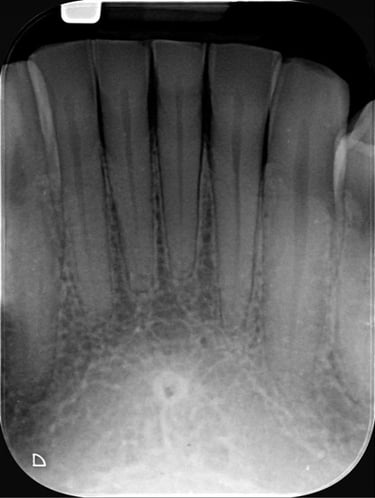

Intraorales

ofrecemos RX a través de pequeñas placas radiográficas, en la parte interna de la boca, las cuales se presionan a través de nuestros equipos de RX externo, logrando una imagen digital, facilitando el proceso, haciéndolo mucho más eficiente .

- Periapical: Se utilizan para explorar todo el diente (corona y raíz y el hueso de soporte).

- Periapical Completo: Se toma radiografía en varias placas de todos los dientes seriados de maxilar superior e inferior para su análisis.